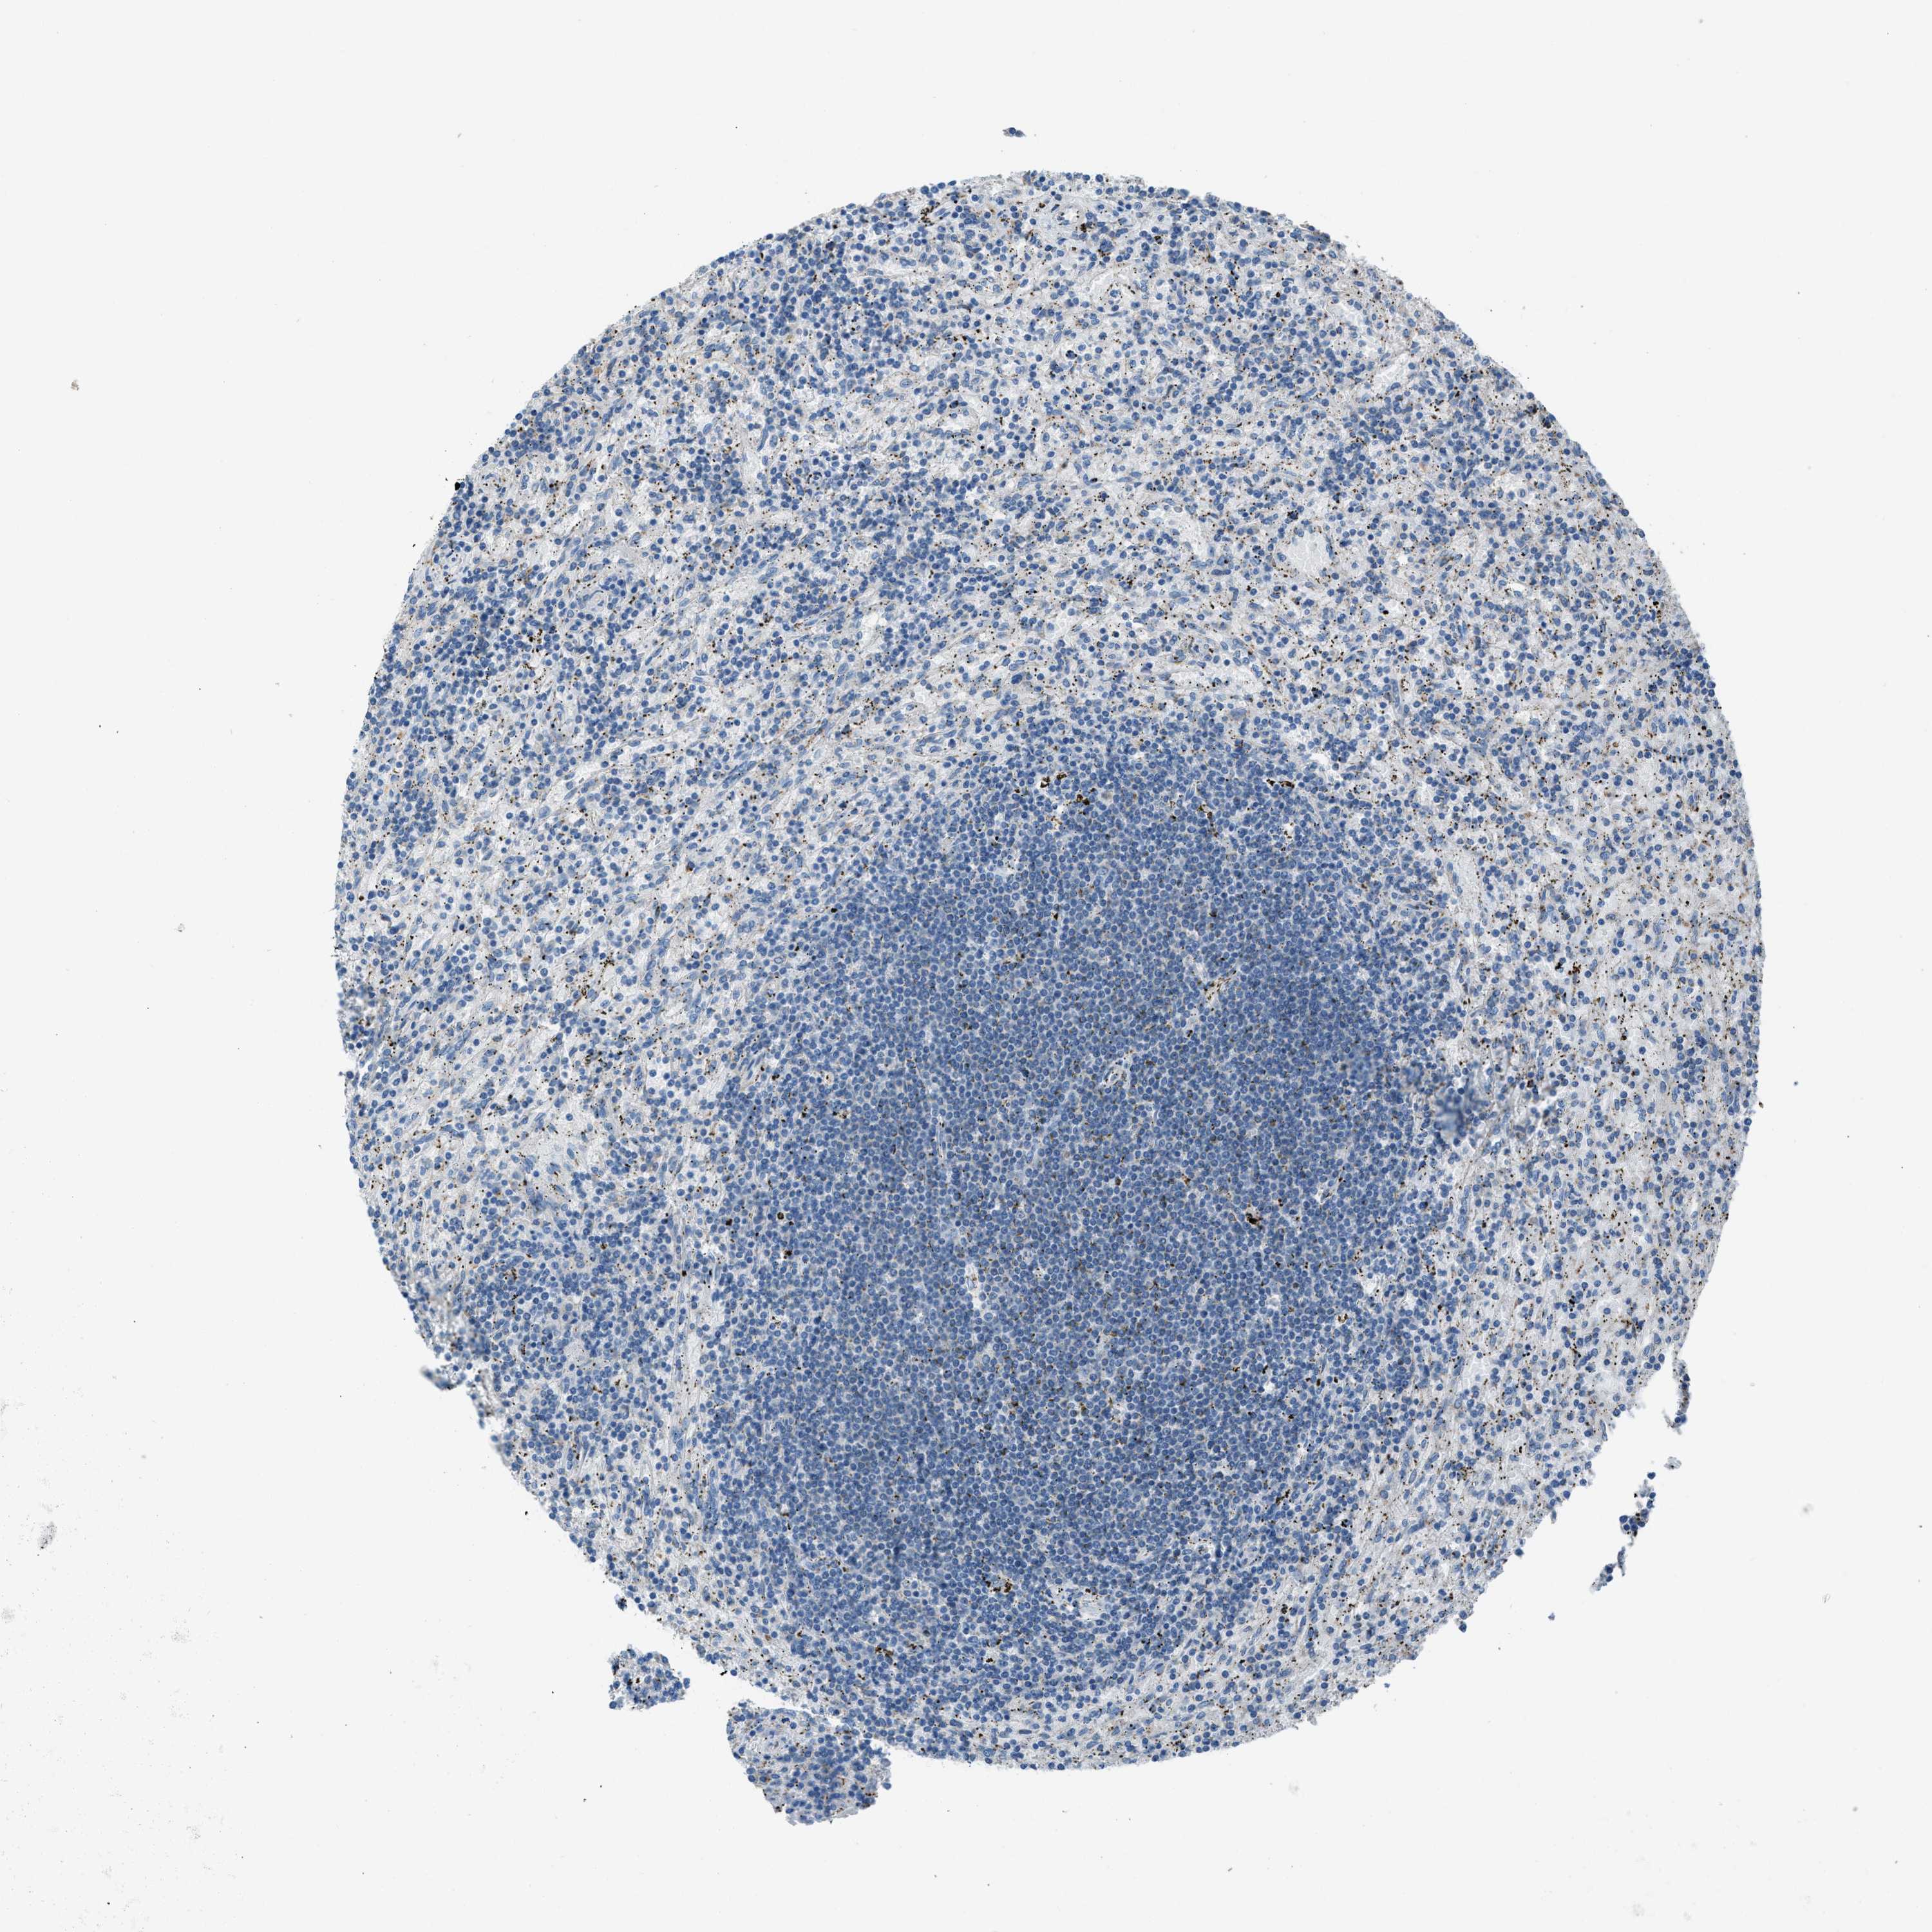

LYMPHOMA - Protein expressioni

A mouse-over function shows sample information and annotation data. Click on an image to view it in a full screen mode. Samples can be filtered based on level of antibody staining by selecting one or several of the following categories: high, medium, low and not detected. The assay and annotation is described here.

Antibody stainingi

Antibody staining in the annotated cell types in the current human tissue is reported as not detected, low, medium, or high, based on conventional immunohistochemistry profiling in selected tissues. This score is based on the combination of the staining intensity and fraction of stained cells.

Each image is clickable and will lead to virtual microscopy that enables deeper exploration of all samples and also displays staining intensity scores, fraction scores and subcellular localization as well as patient and tissue information for each sample.

Antibody HPA016552

Staining

High

Medium

Low

Not detected

Intensity

Strong

Moderate

Weak

Negative

Quantity

>75%

75%-25%

<25%

None

Location

Nuclear

Cytoplasmic/membranous

Cytoplasmic/membranous,nuclear

Hodgkin's disease, NOS

Malignant lymphoma, non-Hodgkin's type, High grade

Malignant lymphoma, non-Hodgkin's type, Low grade